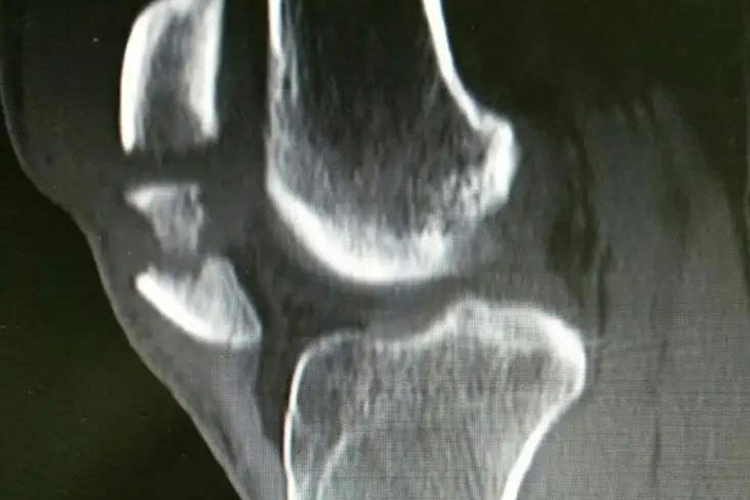

髌骨撕脱性骨折受伤后,膝前方肿胀明显,有瘀斑,膝关节不能活动。查体可见髌骨前方有压痛感,受伤早期可扪到骨折分离出现的凹陷,挤压髌骨使疼痛加重。由于骨折后关节内积血,可见浮髌试验阳性。通过X线检查可见髌骨的完整性被破坏,一部分髌骨完全断裂撕脱。